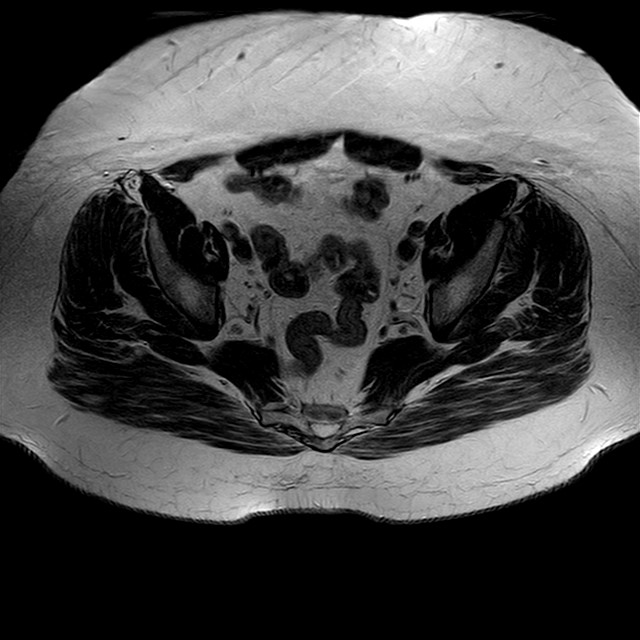

Esami: RMN BACINO

eT2w TSE

Evidenti e simmetriche alterazioni osteofitosiche in regione coxo femorale con riduzione delle rime articolari. Degenerazione completa del cercine glenoideo. Non attuali segni di versamento articolare. Non segni di edema osseo che escludono attuale algodistrofia od osteonecrosi. Lieve e simmetrica riduzione del trofismo della muscolatura glutea.